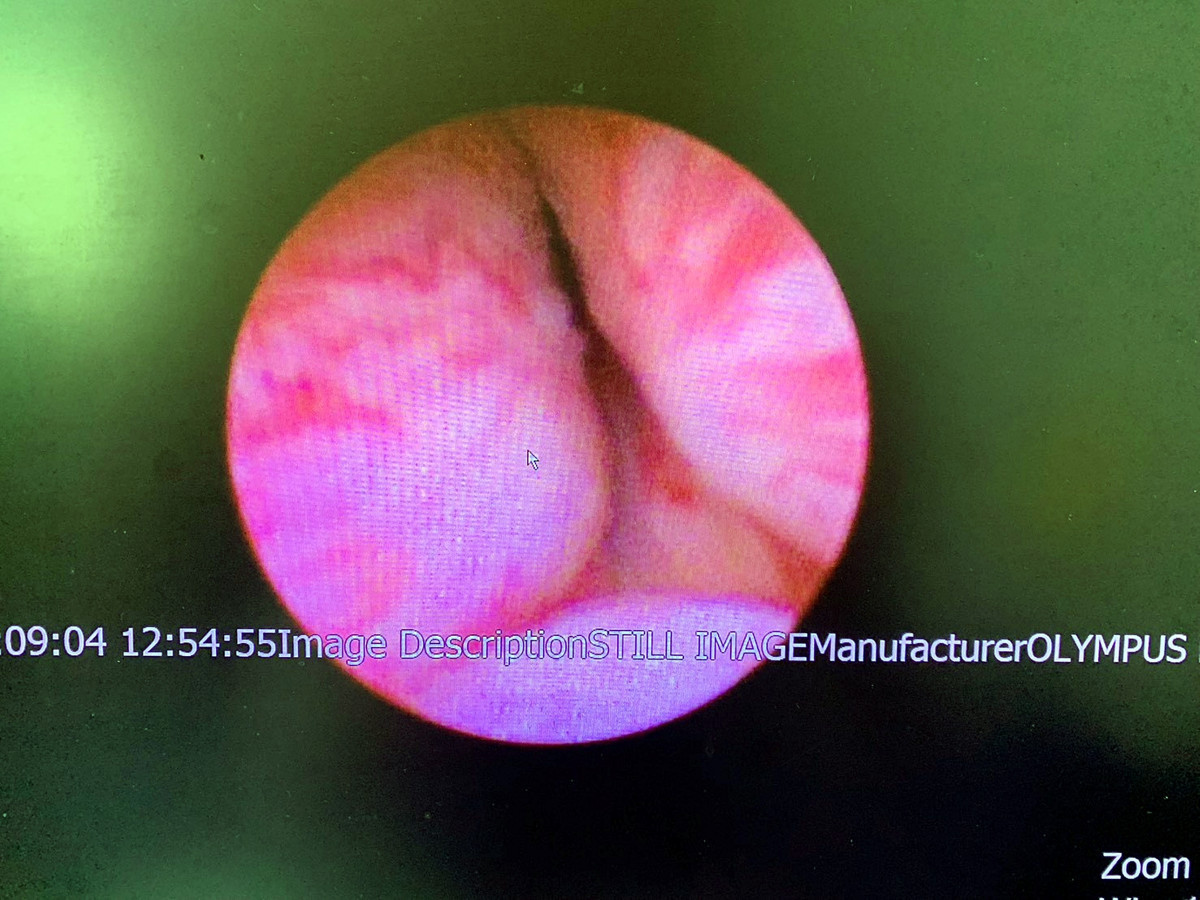

另有 66歲的

L先生,本身有僵直性脊椎炎,長期頻尿及小便解不乾淨,診斷為攝護腺肥大(大約48cc),於門診治療,服用攝護腺放鬆及縮小藥物後,排尿也沒有顯著改善,有考慮手術治療,但擔心出血風險。後來,在醫師建議下接受攝護腺拉開手術(如圖三及圖四),術後不僅沒有血尿情形,小便也恢復暢通,並完全停用攝護腺肥大藥物。

「攝護腺拉開手術」是一種微創、相對安全的新選擇。劉家翔主任進一步說明,此手術是經由內視鏡,將鎳鈦合金的釘子植入攝護腺肥大的腺體,造成擠壓進而拉開尿路,後續攝護腺組織會因擠壓造成的缺血產生萎縮,尿路即可長期保持通暢;因為手術過程並無加熱切割或是破壞組織,所以不會造成出血、結疤,也不影響射精與勃起功能。